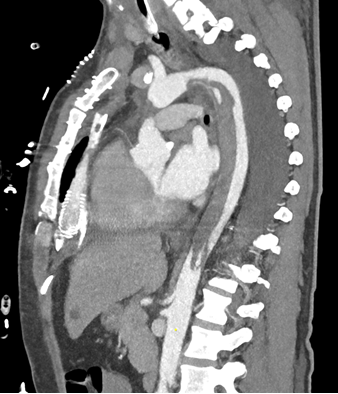

49-year-old male was transferred to our center to be evaluated for LVAD implantation and possibly HTx listing after receiving ECMELLA therapy in an external hospital due to a large anterior STEMI with cardiogenic shock. After neurological evaluation via perfusion-cCT and informed consent of the family he was planned for LVAD implantation on day 7 after the myocardial infarction. In the days before the surgery, patient received therapy of a pneumonia and the pulmonary edema resulting from the cardiogenic shock. Surgery went uneventful without any complications. Right heart function was satisfactory, so there was no need for right heart assist device. ECMELLA was explanted intraoperatively. On postoperative day 3, the patient showed signs of rhabdomyolysis and symptoms of malperfusion of the left leg as well as possible malperfusion of the abdomen. CK was 23.533 U/l, although CK-MB was initially normal. Hs-Troponin was in decline, reaching values of 71670 pg/ml (peak: 244630 pg/ml on day 0 postoperatively) Myoglobin was 61711 µg/l and liver enzymes were highly elevated (GLDH: 9895 U/l, GOT: 5184 U/l, GPT: 3577 U/l). Therefore, a CT-angiography was performed revealing a large descending thoracic aortic thrombus (DTAT, length approx. 20 cm, beginning distal of the left subclavian artery expanding downwards until the coeliac trunk). Thrombus formation was most likely the result of the watershed caused by ECMELLA therapy and the thrombogenicity of the IMPELLA device itself as an extreme form of a Harlequin syndrome. Medical therapy with heparin was inducted, target aPTT was set to a minimum of 60 seconds. In the following week, CK and myoglobin returned to preoperative values under the use of continuous renal replacement. In the following days in ICU, even though distal leg perfusion was installed on the day of receiving ECMO, the patient showed increasing malperfusion of the left leg where the IMPELLA used to be in place. After a couple of days, a clear demarcation was seen and our vascular surgery colleagues recommended amputation of the left thigh. ICU stay was prolonged due to several complications including dialysis due to the renal impairment, pneumonia and wound healing disorder/lyphatic fistula following the amputation. After admission to the ward on postoperative day 52, the patient did well and after permission of the vascular surgeons cumarine therapy was inducted. On postoperative day 60, bridging with heparin was stopped when an INR of greater than 2 was achieved. A follow up CT-angiography on day 74 revealed complete remission of the DTAT.

Figure 1

Figure 1: Large descending thoracic aortic thrombus beginning distal of the left subclavian artery expanding downwards until the coeliac trunk